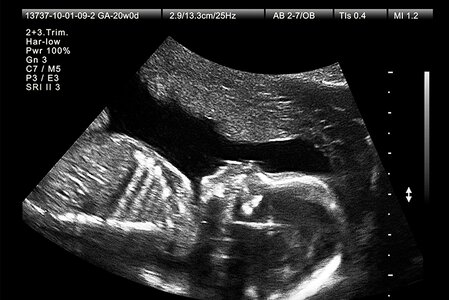

Đình chỉ hành nghề khám bệnh, chữa bệnh đối với người có hành vi thông báo, tiết lộ giới tính thai nhi để phá thai. Việc đình chỉ hành nghề khám bệnh, chữa bệnh thực hiện theo quy định của pháp luật về khám bệnh, chữa bệnh.

Cụ thể, thay vì khuyến khích mỗi cặp đôi chỉ có từ 1 đến 2 con như quy định cũ, luật mới trao quyền tự quyết về thời gian sinh con, số con và khoảng cách giữa các lần sinh phù hợp với lứa tuổi, tình trạng sức khỏe, điều kiện học tập, lao động, thu nhập và nuôi dạy con của mỗi cá nhân, cặp vợ chồng trên cơ sở bình đẳng.